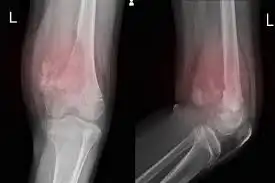

Penting untuk segera mendeteksi dan mendiagnosis osteosarkoma agar pengobatan dapat dimulai dengan cepat. Dokter akan melakukan serangkaian tes, termasuk pemeriksaan fisik, pencitraan seperti X-ray dan MRI, serta biopsi untuk memastikan diagnosis.